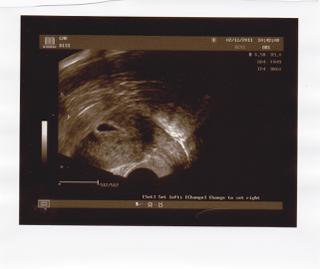

Vidím ho krásně! A dokonce z polední moči! Super!

Ahojky holky, tak náš první ultrazvuk nás čeká 2.11 😀 těším se i bojím zároven 😀 ale tyhle pocity jsou asi normální, u Danielky sem to tolik neprožívala, těhotenství my v 16 letech přišlo tak automatické, za to ted, hysterka hadr 😀 😅 😅 😅 😀 😀 😀 no já se modlím, abysme uviděly tu krásnou blikající tečku 😀

My valíme ve čtvrtek už na 2 screening, tak se těšíme, že princeznu uvidíme, bo moje mudra bohužel utz nedělá, i když po tom co malá každodenně kope jak kdyby hrála za první ligu, tak mi to tak nevadí, radši ji cítím, než ji vidět jen pět minut na malé obrazovce. Snad bude všechno v pořádku, tak se taky opatruj a zítra hodně štěstí a pěknou fotečku ať tu máme pa pa